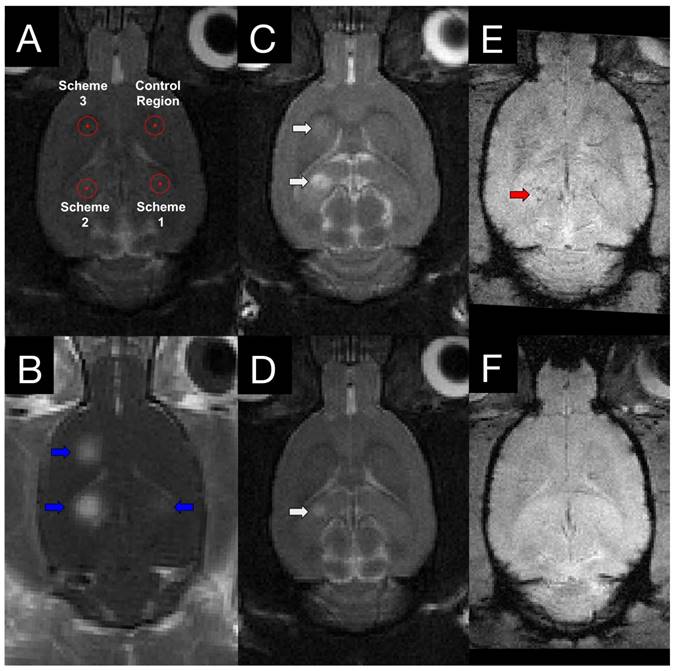

T2w and T2*w MR images were acquired for all animals at 4 h post-FUS and in group 2 animals at 4 days post-FUS (Figure 2). Edema was evident on T2w images in 0/8, 6/8, and 4/8 animals for schemes 1, 2, and 3, respectively, at 4 h following sonication. Only one animal displayed edema at 4 days post-FUS, in a location sonicated with scheme 2 (Figure 2D). Microhemorrhage, as indicated by hypointense regions on T2*w images, was observed in one animal at 4 h and no animals at 4 days following sonication. The one region of microhemorrhage was observed at a target sonicated with scheme 2 and was the same region that displayed edema 4 days post-FUS (Figure 2E).

Figure 2

MRI targeting and post-FUS imaging. (A) Targets for sonication were chosen from T2w images. To mitigate the variance between different regions of the brain, the schemes were rotated around the 4 target regions within each group. (B) Contrast-enhanced T1w images illustrate regions of increased BBB permeability (blue arrows) in the targeted locations. 4 h (C) and 4 days (D) following sonication, edema (white arrows) is evident on T2w images at locations sonicated with scheme 2 and 3. T2*w imaging was also performed at 4 h (E) and 4 days (F) post-FUS. Evidence of hemorrhage (red arrow) was observed in one animal.